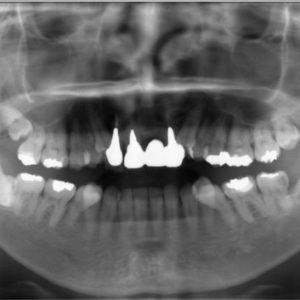

虫歯の治療、矯正の相談をご希望され来院されました。お口の中を診査(レントゲン写真、口腔内写真、視診)させていただいたところ、虫歯については問題なくきれいに歯磨きされているようでした。 正面から見るとジグザグしており、お口 […]

全体的な歯並びの矯正治療を行いました。治療期間は3年間。

ジグザグの歯並びを気にされてご来院されました。. 見た目の問題も大切ですが、それ以上に清掃がしにくいために虫歯・歯周病に非常になりやすく、不正咬合(良くないかみ合わせ)は顎の関節に負担をかけてしまい顎関節症を引き起こす可 […]

歯の大きさに対する顎の大きさのスペース不足により歯が並びきらず、ジグザグの歯並びおよび上の前歯が出っ歯になっていました。 左右4番の歯を抜歯することにより歯を並べるスペースを確保し、歯並びを揃えました。 全体の歯並びが綺 […]